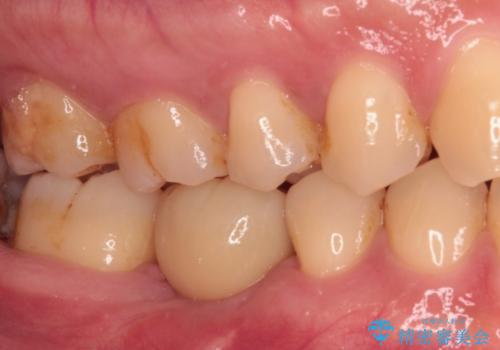

平日の昼間でもご来院可能とのことであったので、必要最小限の期間で治療を終えることができました。